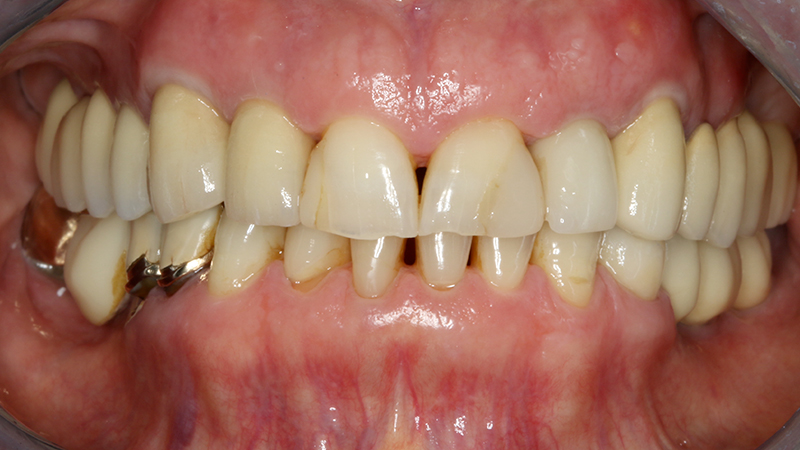

La paziente, di 68 anni, buona salute generale, presentava un grave problema al ponte 17-15-14 con dolore alla masticazione, mobilità e grave perdita ossea su 17 e 12 (Figs. 1, 2, 3).

Si procedeva inizialmente registrando in digitale la biocopia del ponte (STL) per conservare la posizione esatta dei denti da ricostruire, rimozione del ponte e del dente 17 riapplicando il ponte come provvisorio segnadolo distale al 14 ed estraendo il 17 (Fig. 4).